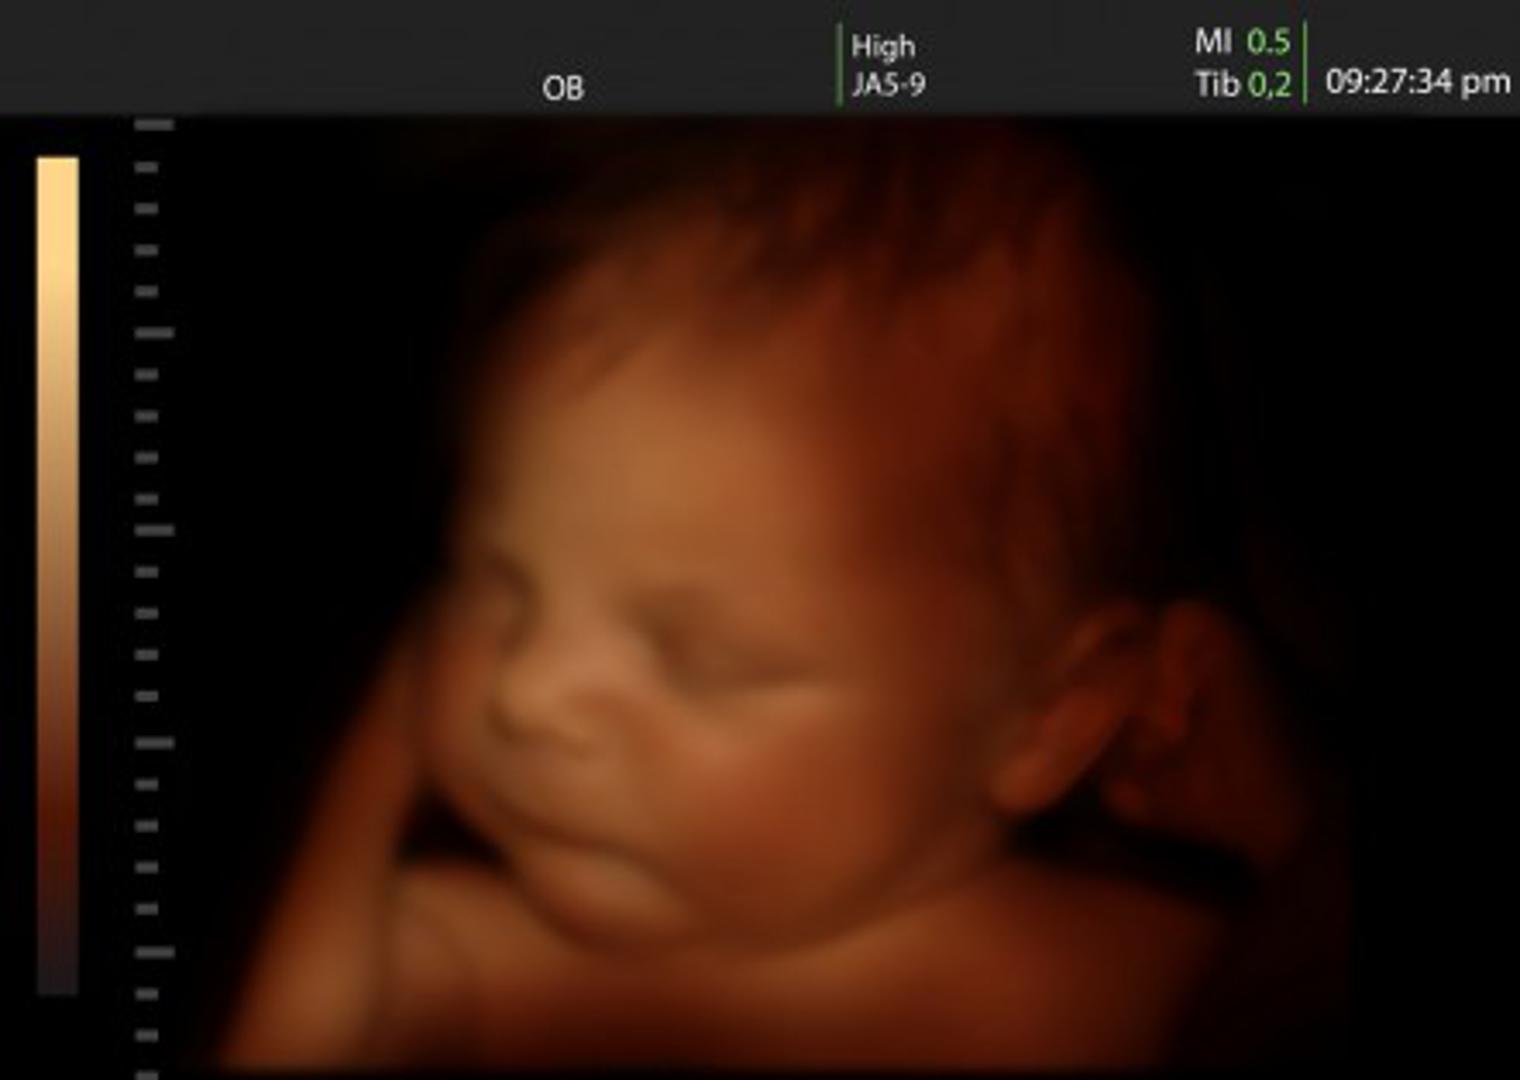

4D ultrazvuk